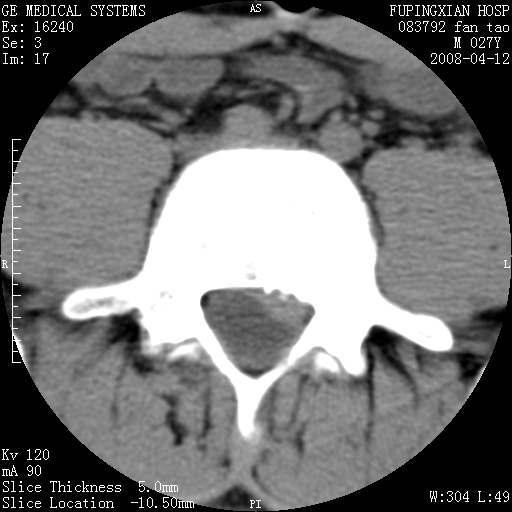

以下是引用前行在2008-4-13 13:53:00的发言:[br]椎间盘髓核终板下突出形成许莫氏结节及椎间盘突出,建议mr检查

以下是引用xclzq_910在2008-4-13 12:43:00的发言:[br]这个应该没什么了,椎间盘突出后反应性骨质吸收硬化.建议mr